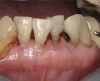

There are several advantages of using SDF in dental treatment. First, it showed an antimicrobial activity against mono-species, dual-species, and multi-species cariogenic biofilm.14-16 Silver ions are bactericidal metal cations that inhibit biofilm formation.17 Studies have indicated that silver interacts with sulfhydryl groups of proteins and DNA, thus altering hydrogen bonding and inhibiting respiratory processes, DNA unwinding, cell-wall synthesis, and cell division.18 At the macro level, these interactions affect bacterial killing and inhibit biofilm formation.17 Second, fluoride promotes caries lesion remineralization. Fluoride has been indicated to react with hydroxyapatite and generate calcium fluoride, which is a reservoir of fluoride, and facilitate further remineralization.19 An ex vivo study reported surface microhardness of the surface layer of the arrested caries after SDF applications was comparable with the unaffected sound dentin20 (Figure 1 and Figure 2). This is consistent with another study, in which a high remineralized zone was observed on the surface of arrested caries from exfoliated teeth with SDF treatment21 (Figure 3 and Figure 4). Third, its application procedures are simple and do not require injection or drilling, and the treatment does not involve expensive support infrastructure equipment such as piped water and electricity. The simplicity of the treatment is conducive to treating caries in apprehensive young children who may have intense dental fear, uncooperative patients with special needs, or elderly patients who have difficulty adapting to traditional dental care. It also allows trained workers to deliver the treatment to people who live in the area but who may not be able to easily access dental service.22 Patient compliance and satisfaction is often good when the patient is provided a clear explanation of the treatment outcome.23,24 Finally, the cost of SDF treatment is low and should be affordable in most communities.

The inherent disadvantage of SDF is that the caries lesions will be stained black after SDF application. SDF stops caries progression by forming a hard, blackened, impermeable layer on the tooth surface that is resistant to caries (Figure 5 through Figure 9). The authors’ clinical observations are that the darker the color, the more likely the caries arrested. Some patients may not be pleased with the esthetics of this treatment outcome; therefore, it is important to inform the patients and parents (for child patients) about this treatment outcome. Moreover, SDF can stain clothes and the skin of the body. Though it does not cause any pain or damage, an SDF stain on skin cannot be easily washed away. It takes around 7 days for it to disappear, and the stain on clothes is permanent.22